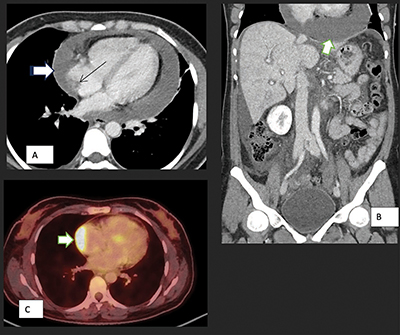

Figure 1

Axial (A) and coronal (B) CT scan images show pericardial effusion (white arrow) and enhancing pericardium, evidence of right heart failure with IVC enlargement and periportal oedema, features of early cardiac tamponade. The thin arrow points to the soft tissue mass in the atrium.

Axial PET-CT (C) shows pathological metabolic activity in the known mass in the right atrium (arrow) extending along the pericardium with intensely increased FDG uptake.